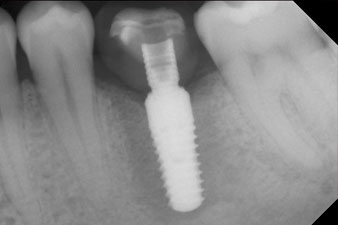

Имплантът е поставен както е планирано след цялостно отстраняване на гранулационната тъкан (blueSky, bredent).

Въртящият момент, използван за машинно-задвижвано поставяне, е 43 Ncm. Освен това, след завинтване на измервателния щифт (SmartPeg), специално пригоден за импланта, стойността на ISQ се измерва със сондата на W&H Osstell ISQ модула.

Този модул е допълнителна екстра към Implantmed на W&H и е закачен към имплантологичния мотор (виж фиг. 11). Липсата на ISQ стойност непосредствено след поставянето е 64 оровестибуларно и 68 мезиодистално (максимална стойност = 100).

Тези стойности могат да показват отворено лечение или дори имедиатно възстановяване. Поради недостатъчния обем на кресталната кост при импланта, областта е подсилена с костните частици, събрани по време на препарацията на имплантното ложе и зашити, за да се изолира слюнката.